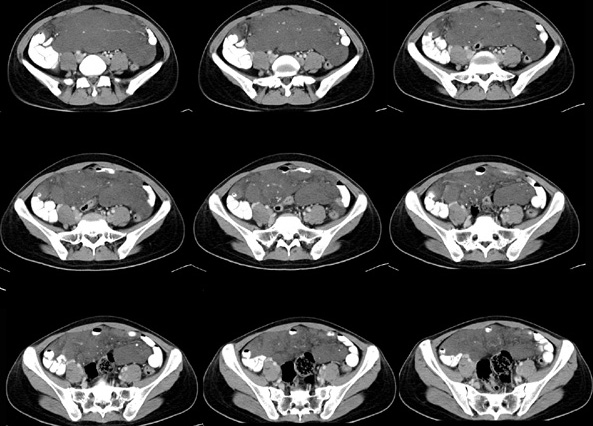

女性,28岁,停经3月,腹部膨隆1月,产前检查发现腹部占位

{肿块中心ct值27hu,增强后,动脉期、门脉期均无明显强化)

1 肠系膜肿块诸期无明显强化,肠系膜血管包绕其中但其周围仍见脂肪称“脂肪环征”;2 肠系膜血管远端较近端细,于重组像上见血管周围有强化结节为炎性结节,3肿块内见部分脂肪密度及少许点状钙化。4 腹膜后无肿大ln。

需与恶性病变鉴别,脂肪环征为重要点。亦需与卵巢源性肿瘤鉴别,年龄以及未见“卵巢静脉征”为要点。

患者手术病理:腹腔囊性淋巴管瘤,象这样充满整个腹腔的的确很少见